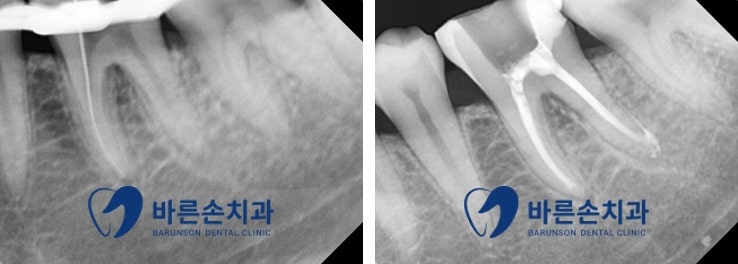

2~3회에 걸쳐 신경치료 진행하였고

신경치료 완료 후 엑스레이를 통해

신경치료가 깨끗하게 잘 된 것을 확인하였습니다

가장 중요한!! 환자분의 통증!!

환자분께도 통증이 나타나지 않음을 확인하고 신경치료가 마무리되었습니다^^